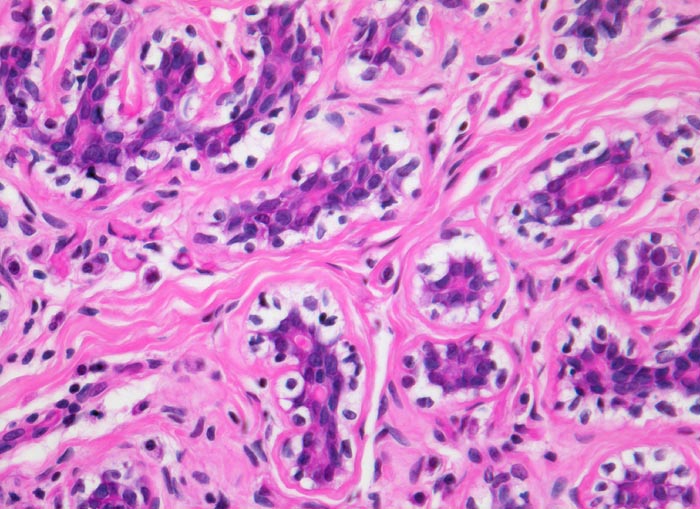

Morphologische Merkmale:

• Zwei scharf begrenzte Tumorknoten.

• Biphasischer organoid aufgebauter Tumor bestehend aus kompaktem zellarmem fibroblastärem Stroma, das in konzentrischen Lamellen um verzweigte, miteinander anastomosierende Drüsenschläuche angeordnet ist.

• Die Drüsenschläuche werden durch das Stroma komprimiert.

• Das Stroma erscheint herdförmig bläulich und aufgelockert durch Muzineinlagerungen.

• Stellenweise gewöhnliche intraduktale Epithelproliferation ohne Atypie.

• Die Drüsen werden ausgekleidet von einer inneren kubischen bis hochprismatischen Zellschicht und einer äusseren abgeflachten Myoepithelschicht mit klarem Zytoplasma.